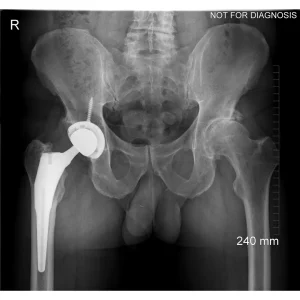

A total hip replacement (also called total hip arthroplasty) is a surgical procedure in which a damaged or worn hip joint is replaced with artificial components. The hip is a ball-and-socket joint, meaning the ball at the top of the thigh bone sits in a socket on the pelvis. During surgery, the damaged ball (femoral head) is replaced with a metal or ceramic ball attached to a stem, and the damaged socket is replaced with a metal cup lined with plastic, ceramic, or metal.

- The surgeon removes the damaged bone and cartilage and inserts the artificial joint